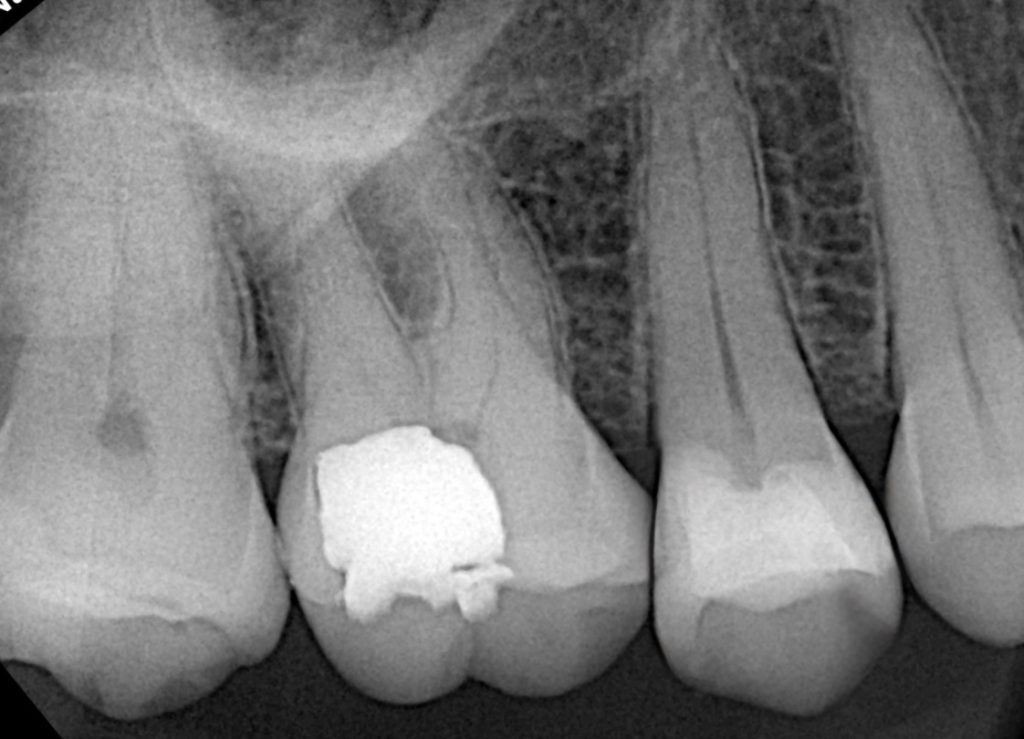

Clinical and radiographic exam confirmed adjacent Class II carious lesions affecting both teeth, with secondary caries beneath existing composite and defective margins.

2. Caries Removal & Margin Management

Defective composite and caries were removed in a controlled manner preserving sound enamel walls. Teflon floss ties and wooden wedges used for separation and gingival retraction (Fig 3–6).

- Initial caries exposure and removal

- Proximal clearance and wedge placement